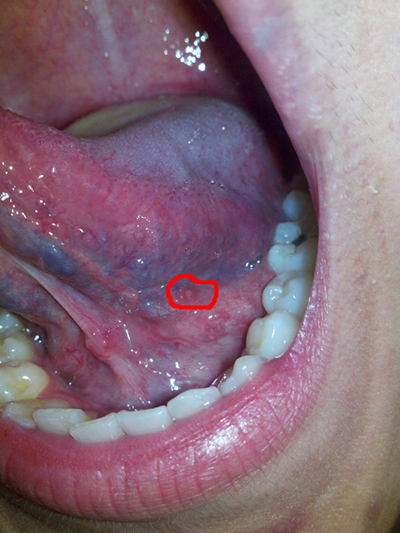

舌癌圖片

A:舌癌一般是在舌側緣出現腫物,有外生型、潰瘍型和浸潤型。最常見的是外生型和潰瘍型,一般在早期就是在舌側緣出現一個深的潰瘍,而且潰瘍長期不愈。和普通的口腔潰瘍不同,舌癌的潰瘍兩個月以上也不會自行癒合,創面不斷的增大、加深,加深到一定程度舌頭會出……

A:舌癌是口腔頜面部常見的一種惡性腫瘤,多數為鱗狀細胞癌,多見於舌緣,常為潰瘍型或浸潤型,增長快,疼痛明顯,浸潤性強,可導致舌運動受限,進食及吞嚥困難,男性多於女性。舌癌的病因目前尚不明確,多數認為與環境因素有關,另外,神經因素,內分泌因素,機……